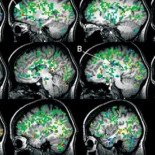

Así reacciona el cerebro de una mujer cuando alcanza un orgasmo

cerebro

,

orgasmo

orgasmo femenino

kayt sukel